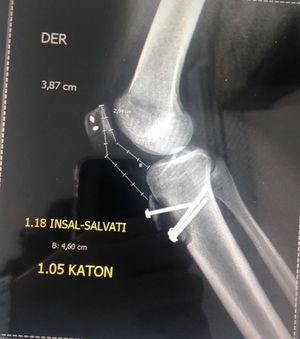

Este es un caso en el que la paciente tuvo una fractura de tibia y para arreglarla le pusieron tornillos. 2 meses después regresa para una revisión, en la cual los doctores se dan cuenta que la fractura ha vuelto y ahora con todo y tornillos.